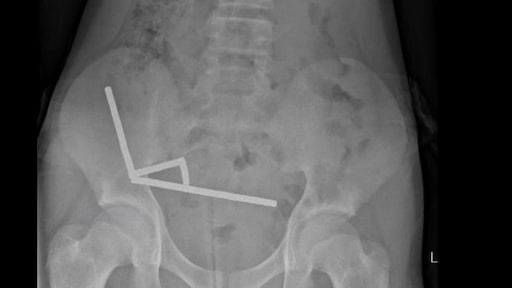

Op de röntgenfoto boven dit artikel zie je hoe de magneten in de darmen van het kind waren samengeklonterd.